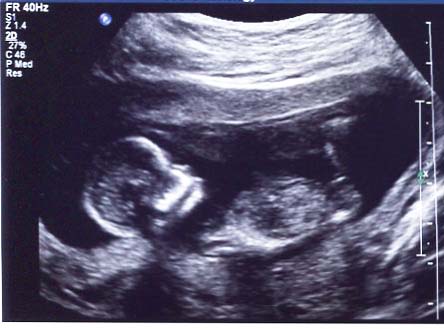

My Scan pictured below was done at 12w6d. The sonographer was pretty sure it's a boy from the potty shot view but unfortunately I didn't get a picture of this (now wishing I had!) Thinking 12 weeks 6 days is still a bit early to tell from potty shots. Appreciate any thoughts / guesses from what you see in the below pic!

Attachment 23717